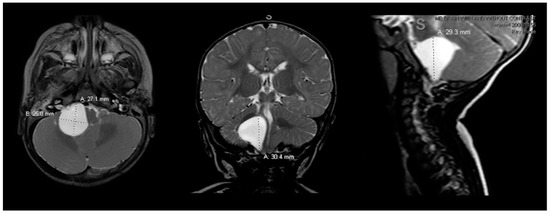

Postoperatively, the patient returned to the pediatric intensive care unit and was extubated. Postoperative rapid-sequence MRI showed a well-decompressed cyst with decreased mass effect on the pons, medulla and cerebellum (Figure 2).

Figure 2.

Postoperative brain MRI scan. The postoperative brain MRI scan on postoperative day 1 (left = axial; middle = coronal; right = sagittal) T2 sequences showed interval decompression of the prior known arachnoid cyst with decreased mass effect. MRI = magnetic resonance imaging.